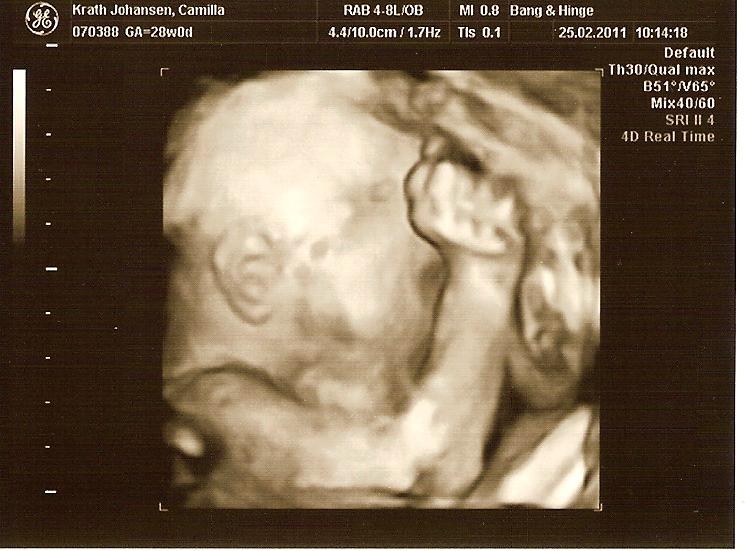

Selvom vores søn var lille, så havde han ikke meget plads at ligge på i uge 30, og da de ligger "lidt klemt", så blir det sværere at se noget, jeg større de blir. Vi fik nogen rigtig gode billeder, men det tog en del tid, fordi hans arme lå presset op foran hans ansigt og det er jo svært lige at flytte dem

Men sikke en stor oplevelse